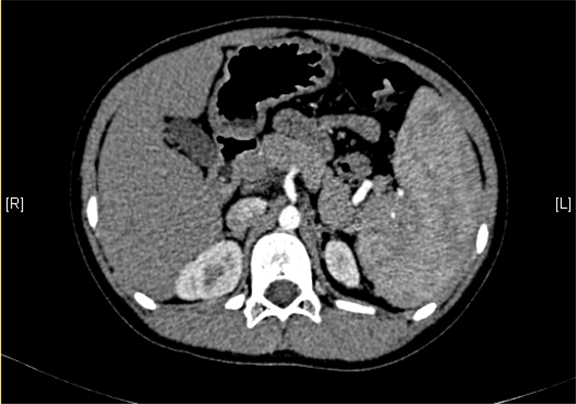

上腹部增强CT:门静脉主干走行迂曲、分支紊乱,考虑门静脉畸形可能性大,不除外门静脉海绵状变性。

术前CT检查:

静脉期